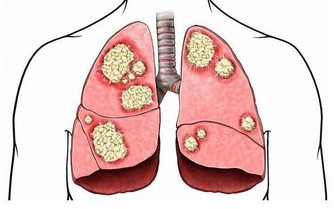

三伏天過去後,夏秋交際的季節,寒溫不調,人體免疫力下降,此時正是肺熱的高發時節,主要是乾咳、痰多、唇部乾燥等現象。

秋季易反复咳嗽咳嗽是一種保護性的反射動作。

但是,持久劇烈的咳嗽不僅影響休息,還會消耗體力,甚至將病變擴散到鄰近的小支氣管,誘發肺炎、肺氣腫等重大疾病。所以,選止咳藥時,要先弄清病因。

專家提醒,秋季燥熱,傷肝傷脾,表現為咳嗽痰多。

所以,如果咳嗽老不好、經常反复就要注意了,這多半是由以下幾個原因引起,一定要對症治療才有效。